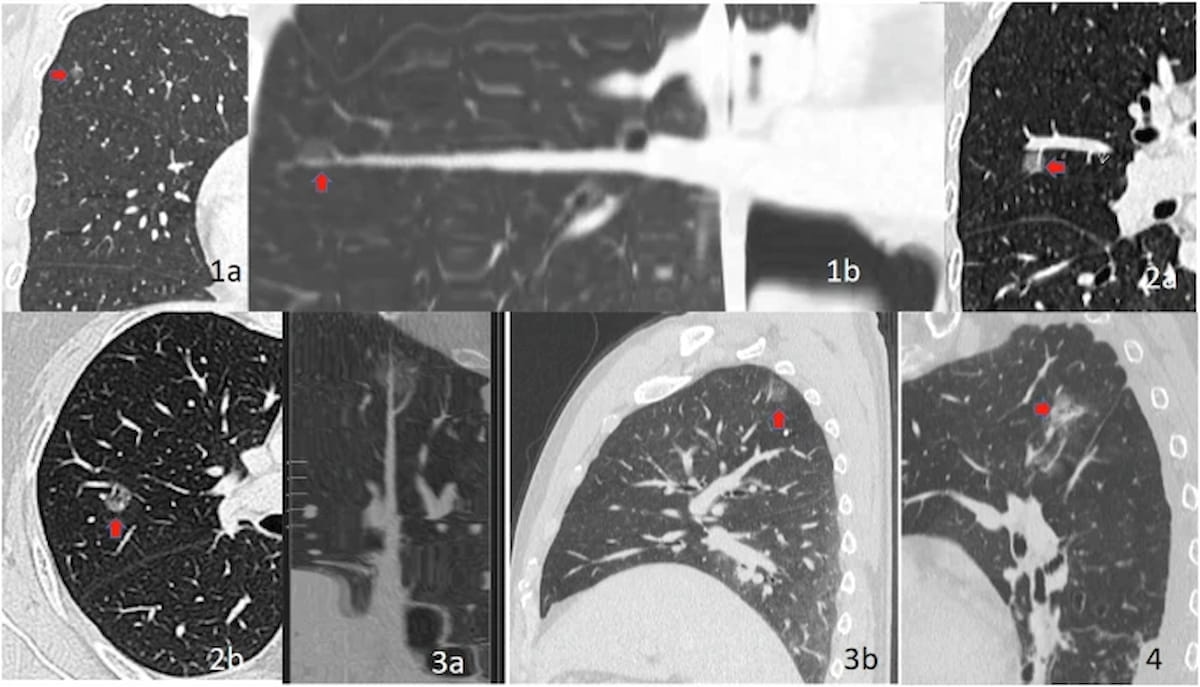

Here one can see different types of ground glass nodule (GGN)-vessel relationships (GVRs) with GVR 1 type (1a, 1b), GVR 2 type (2a, 2b), GVR type 3 (3a, 3b) and GVR 4 type (4). In newly published research, the cLung-RADS v2022 model demonstrated an 87.6 percent accuracy rate in predicting the invasiveness of pure ground glass nodules (pGGNs) on CT scans. (Images courtesy of Insights into Imaging.)